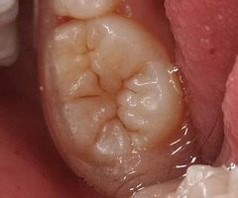

健康的臼齒在咬合面上有許多很深的小窩及小裂溝,食物的殘渣及幼兒的奶垢很容易積存在裡面,成為細菌滋生的溫床,如果未能適時清除乾淨,日積月累,就有可能形成蛀牙。由於臼齒是最常見罹患蛀牙的地方之一,因此牙醫界便採用齒溝封填的技術來預防蛀牙。溝隙封填劑就是用來封填臼齒裂溝的一種液態樹脂材料,將其塗在牙齒表面上以後,再以鹵素燈照射,使其立即堅固硬化,達到封填臼齒齒溝的目的。塗布封填劑後的牙齒,其咬合面不僅可以減少食物的淤積,也能夠讓口腔清潔的工作更容易進行。刷牙刷的乾淨,當然也就不容易蛀牙了。經過10年以上的臨床研究證實,齒溝封填可以有效減少咬合面上的齲齒,而對於剛萌發的牙齒,尤其是恆牙第一大臼齒,預防效果特別顯著。 一般而言,2至3歲乳臼齒長出後,就可以開始做齒溝封填,通常可維持2-3年左右,不過最好還是每半年回診檢查一次,以防止週邊蛀蝕,造成溝隙封填劑脫落而前功盡棄。